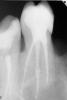

Art 7 Опубликовано 29 сентября, 2013 Автор Поделиться Опубликовано 29 сентября, 2013 (изменено) .jpg] извините за качество Изменено 29 сентября, 2013 пользователем Art 7 Ссылка на комментарий

kriokov Опубликовано 29 сентября, 2013 Поделиться Опубликовано 29 сентября, 2013 Хорошая анатомия для ампутации. По внедрению и последовательности не могу совет дать, не силен. Ссылка на комментарий

doca Опубликовано 29 сентября, 2013 Поделиться Опубликовано 29 сентября, 2013 1.JPG извините за качествода,вроде жалко удалять,а какое расстояние между 23-26 на уровне шеек? Ссылка на комментарий